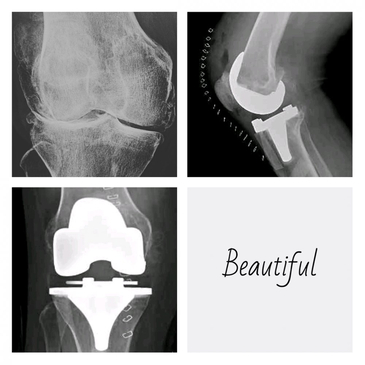

Dr. Rodrigo Aguirre Rojas is the best Orthopedic Surgeon in San Jose del Cabo, Mexico. Book your consultation for Hip and Knee Replacements in Los Cabos, Mexico at PlacidWay. Emergencies like Fractures and Dislocations are also evaluated and treated